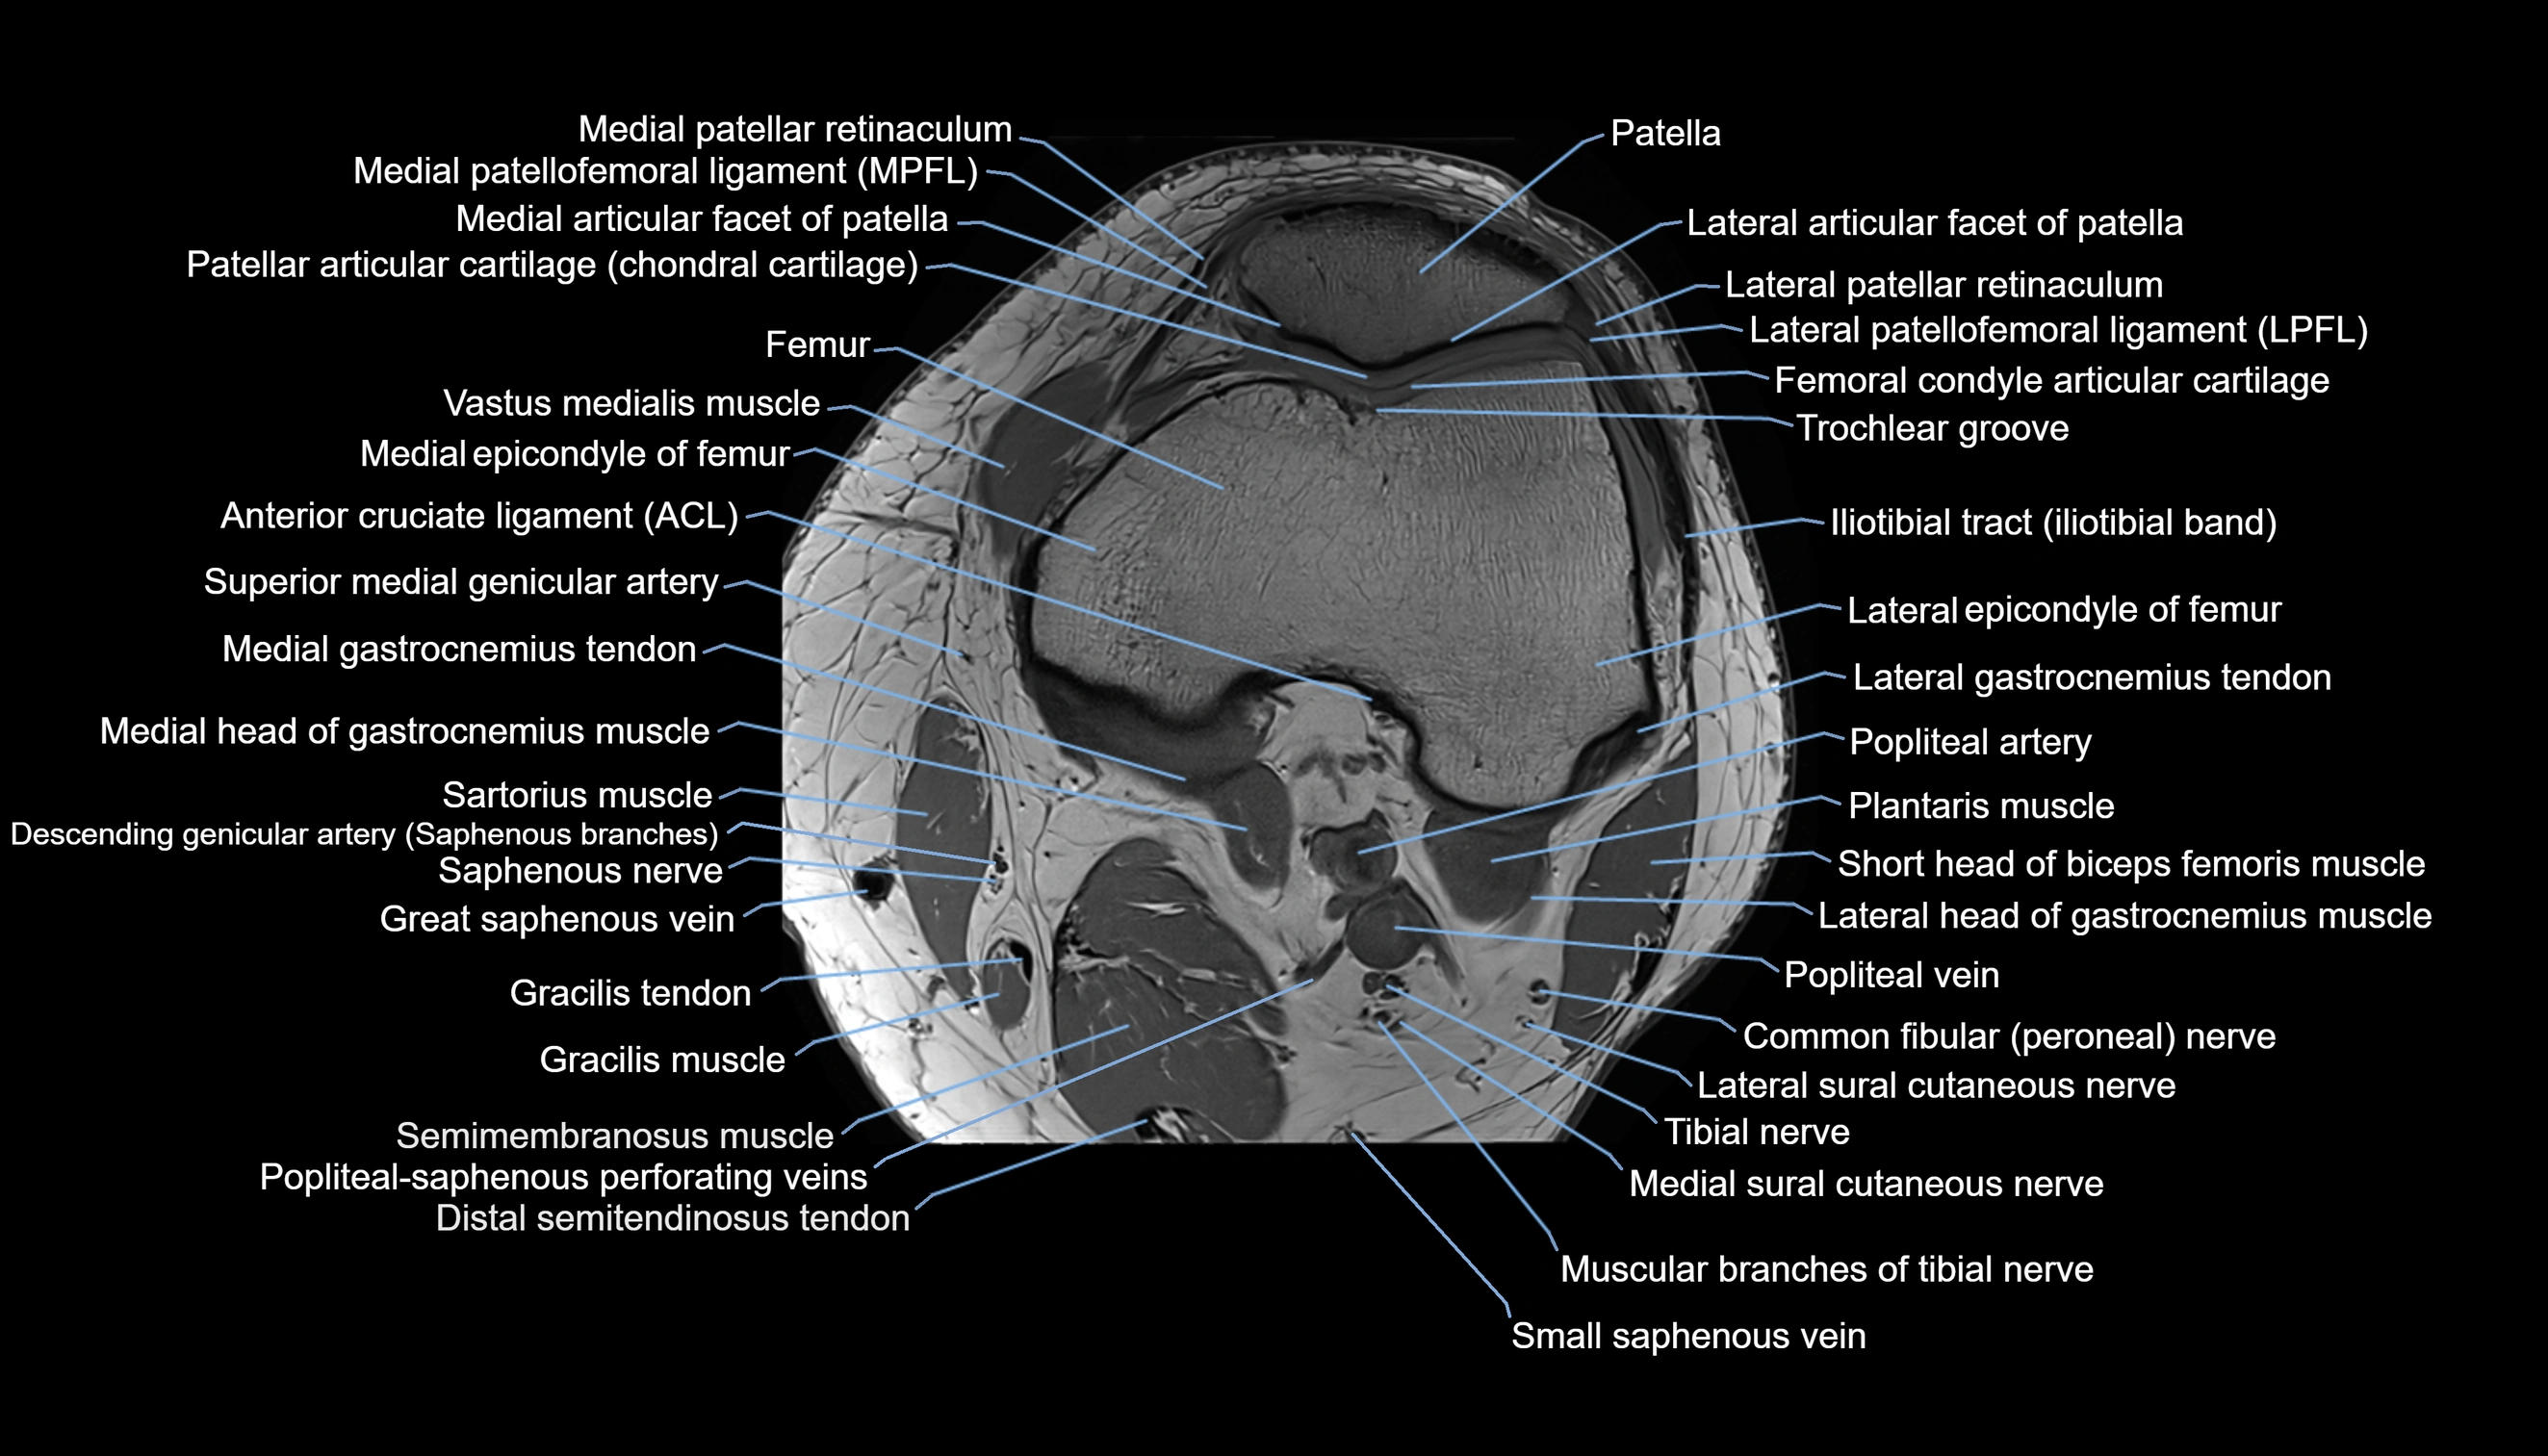

- Anterior cruciate ligament

- Femoral condyle articular cartilage

- Fibula

- Gastrocnemius muscle

- Lateral articular facet of patella

- Lateral border of patella

- Lateral epicondyle of femur

- Lateral gastrocnemius tendon

- Lateral head of gastrocnemius muscle

- Lateral patellar retinaculum

- Lateral patellofemoral ligament

- Lateral sural cutaneous nerve

- Medial articular facet of patella

- Medial epicondyle of femur

- Medial gastrocnemius tendon

- Medial head of gastrocnemius muscle

- Medial patellar retinaculum

- Medial patellofemoral ligament

- Medial sural cutaneous nerve

- Muscular branches of tibial nerve

- Patella

- Patellar articular cartilage

- Popliteal artery

- Popliteal vein

- Popliteal–Saphenous perforating veins

- Saphenous nerve

- Sartorius muscle

- Semimembranosus muscle

- Small saphenous vein

- Soleus muscle

- Tibial nerve

- Trochlear groove

- great saphenous vein